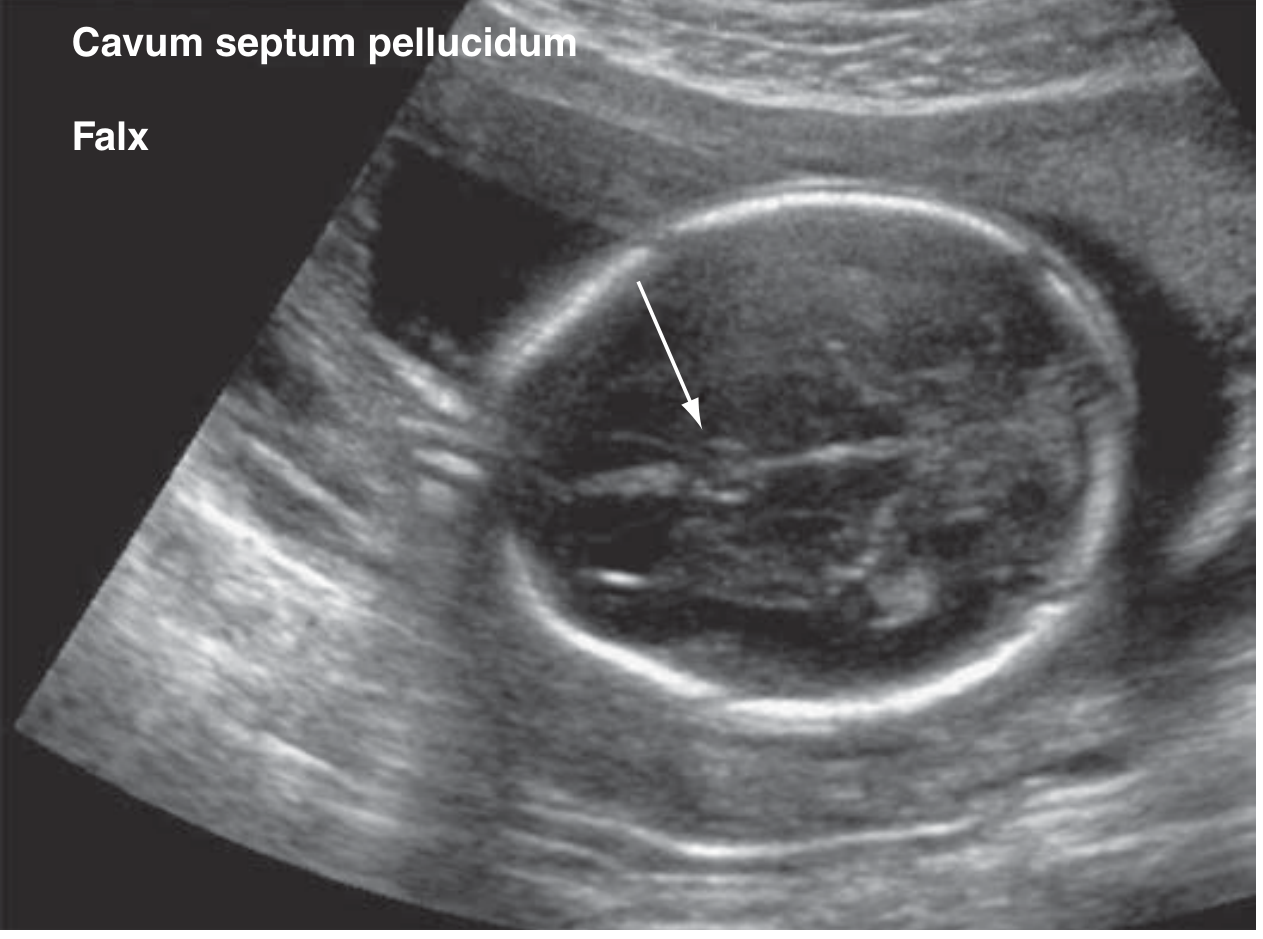

• Cranial bones, falx cerebri, cavum septi pellucidi

Cavum septum pellucidum

Figure: Cavum septum pellucidum (arrow)